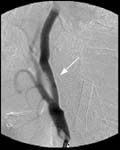

<ÇãÇ÷¼º

³úÁ¹Áß>

ÁÂÃø

Áß³úµ¿¸ÆÀÇ Æó»öÀ¸·Î ÀÎÇÑ ³ú°æ»ö¼Ò°ß(Ç÷°üÁ¶¿µ¼ú»ó

Áß³úµ¿¸ÆÀÌ º¸ÀÌÁö ¾Ê°í ÀÖ´Ù)